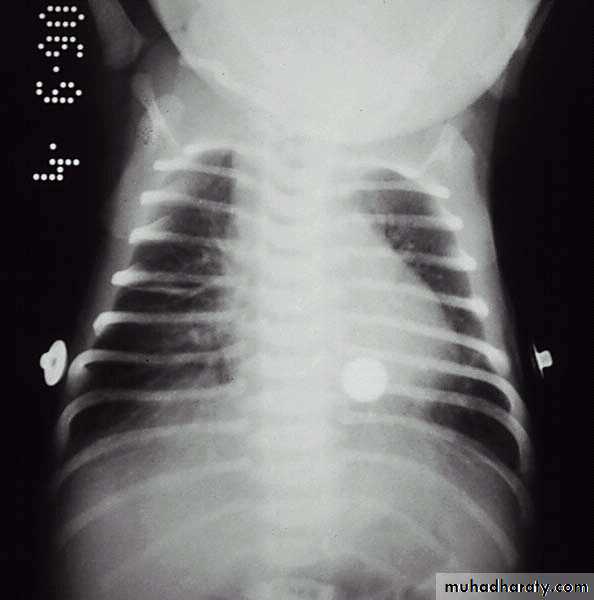

Chest x-ray:Prominent central vascular marking, fluid in lung fissure, overaereation, occasionaly small pleural effusion.

TTN. Radiograph reveals a number of streaky perihilar densities and a visible fluid density in the right major fissure.